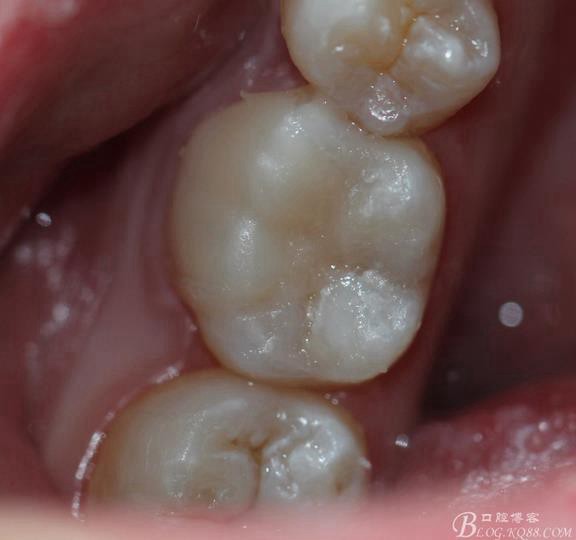

復(fù)診拋光 很容易看到邊緣線(xiàn),原因是主要有兩個(gè):一-瓷塊選擇不準(zhǔn)確,目前我們單位瓷塊顏色單一。二- 粘結(jié)劑,選擇和牙體顏色不一致的。我選擇的偏白,所以邊緣白線(xiàn)較明顯。

總結(jié):歷時(shí)2周時(shí)間結(jié)束,比較累。整體感覺(jué)沒(méi)有想象中那么好,總也做不出樹(shù)脂嵌體的那種渾然天成的感覺(jué)。

我個(gè)人喜歡樹(shù)脂嵌體,樹(shù)脂嵌體的要求沒(méi)有那么苛刻。相比瓷嵌體還能夠保留更多是牙體組織??!這個(gè)是關(guān)鍵。國(guó)外現(xiàn)在做樹(shù)脂嵌體比較多,特別樹(shù)脂直接修復(fù)。做出來(lái)特別有美感,一看到我做出來(lái)的東西美感一點(diǎn)都沒(méi)有。